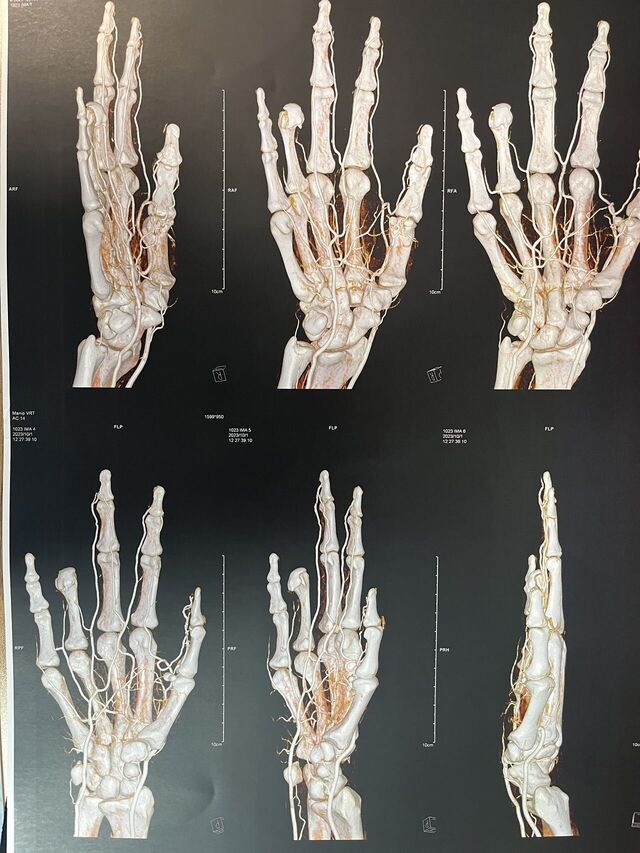

下面是一例示指再造,术后一年10个月随访

微信图片_20230930083837.jpg 微信图片_20230930083849.jpg 微信图片_20230930083851.jpg 微信图片_20230930083851_1.jpg

术后骨折愈合良好

微信图片_20230930075547_1.jpg 微信图片_20230930172958.jpg

术后1年10个月随访